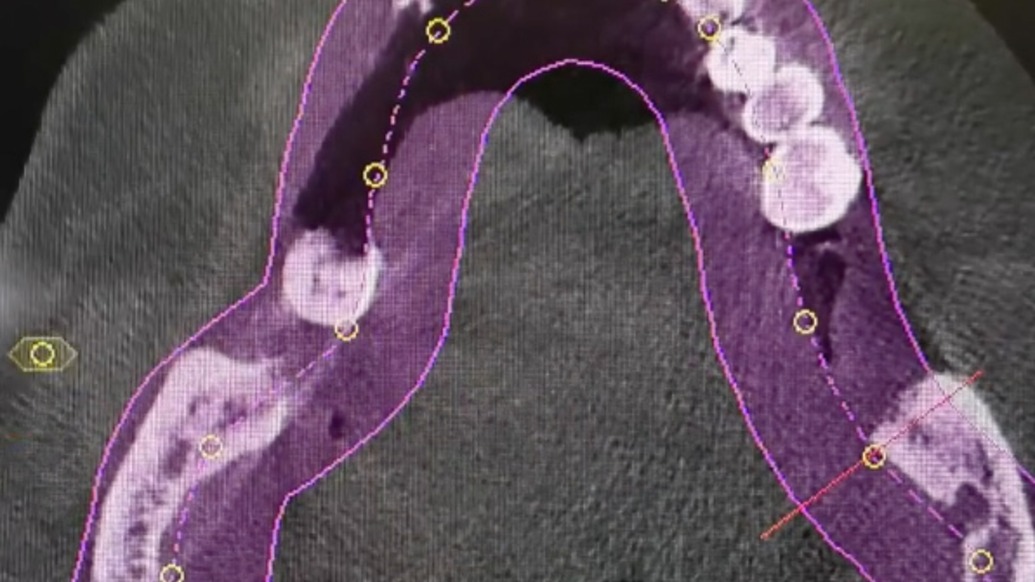

哈尔滨市民刘天娇反映,77岁父亲在门诊拔掉12颗牙齿,又种植6颗牙齿,离店不久吐血离世。涉事口腔门诊负责人称,他们也想知道死因进行定责。卫健部门介入调查。